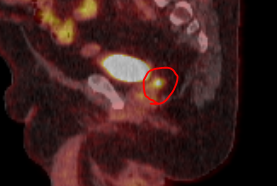

@DrAndrewLoblaw Biopsy to prove recurrence, focal HDR with 6 months ADT. Rectal and urethral dosevusually not an issue when treating the SV.

Here's the scan